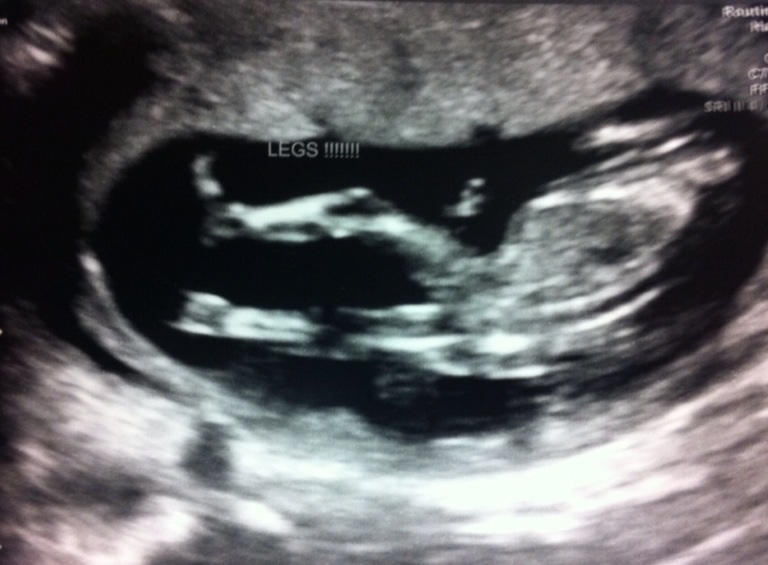

Anyone venture a guess as to what I'm having? 19 week ultrasound is in 2 days but I'm soo impatient!!! :)

Attachment 9585

I can't see a nub and I'm unsure of the potty shot, it kind of looks boyish but could be a girl, I can see where it looks a bit like three bits too. Not sure how your baby will develop and change in the next few weeks. Do you have any clear nub shots?

Looks like boy to me.

looks like boy in first pic, but cant tell from 2nd pic

Looks boy to me :)

I'd say boy